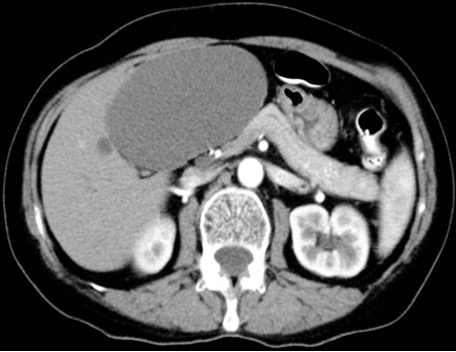

Aspetto TC

- Formazione ben circoscritta, a pareti sottili, ipodensa (0-10 HU), priva di enhancement contrastografico.